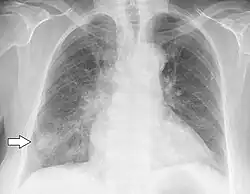

| Chest X-ray of a patient who first had influenza and then developed Haemophilus influenzae pneumonia, presumably opportunistic | |